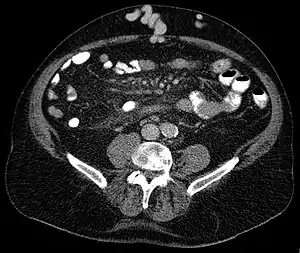

Axial CT showing portosystemic collateral circulation via the umbilical vein: caput medusae in liver cirrhosis | |